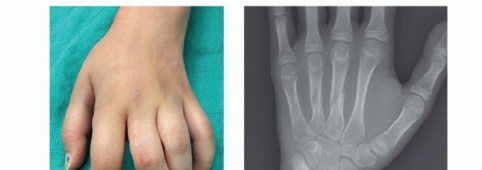

FIG 3 • A. Fracture of the neck of the fifth metacarpal with a flexed, apex dorsal angulation (boxer's fracture). B. Torsional injuries lead to long oblique fractures with a risk for malrotation. C. Short transverse fracture from a direct impact. D. Crush injuries can lead to a combination of injuries with an increased risk of compartment syndrome and significant stiffness. The shortened fourth metacarpal pulls the head of third metacarpal in a proximal and ulnar direction through deep transverse metacarpal ligament. E. Neglected fight bite injury ultimately leading to loss of the metacarpal head. Crush injuries can lead to comminuted fractures with significant soft tissue injuries and a heightened risk of compartment syndrome (FIG 3D).

PATIENT HISTORY AND PHYSICAL FINDINGS

History: Note the mechanism of injury, time since injury, and any treatment received so far. Also, note the age, vocation, and hobbies of the patient. Comorbidities should also be recorded.Inspection: The skin needs to be checked for any signs of an open fracture. A small laceration near the MP joint may be the only sign of a “fight bite” injury which requires urgent débridement to prevent joint and bone infection (FIG 3E). Also, note digit malrotation and extension lag at the MP and proximal interphalangeal (PIP) joints. A severely edematous hand may signal compartment syndrome or an internal degloving injury.Palpation: The neurovascular examination should include checking activation of the first dorsal interosseous muscle to confirm activity of the motor branch of the ulnar nerve. Tense compartments and pain with passive motion may signal a developing compartment syndrome.